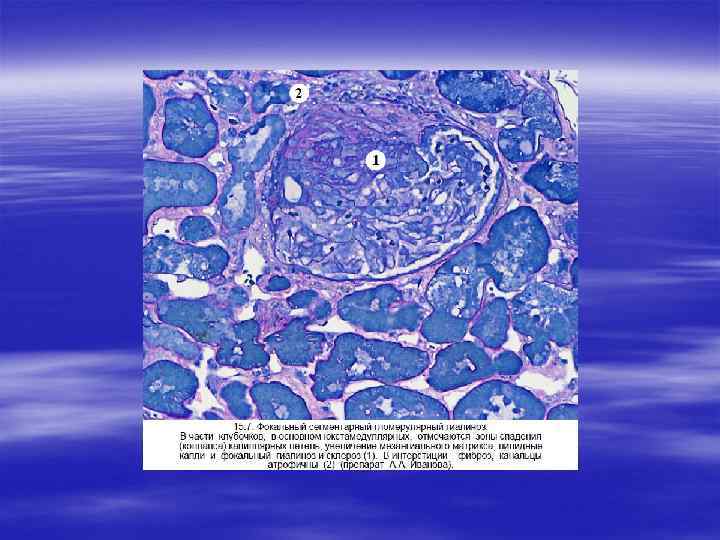

§ Причины нефротического синдрома разнообразны: § системная красная волчанка (люпус нефрит), § диабет, § амилоидоз, § липоидный нефроз (болезнь минимальных изменений), § мембранозный гломерулонефрит,

§ очаговый сегментарный гломерулосклероз, § мембранозно пролиферативный гломерулонефрит.